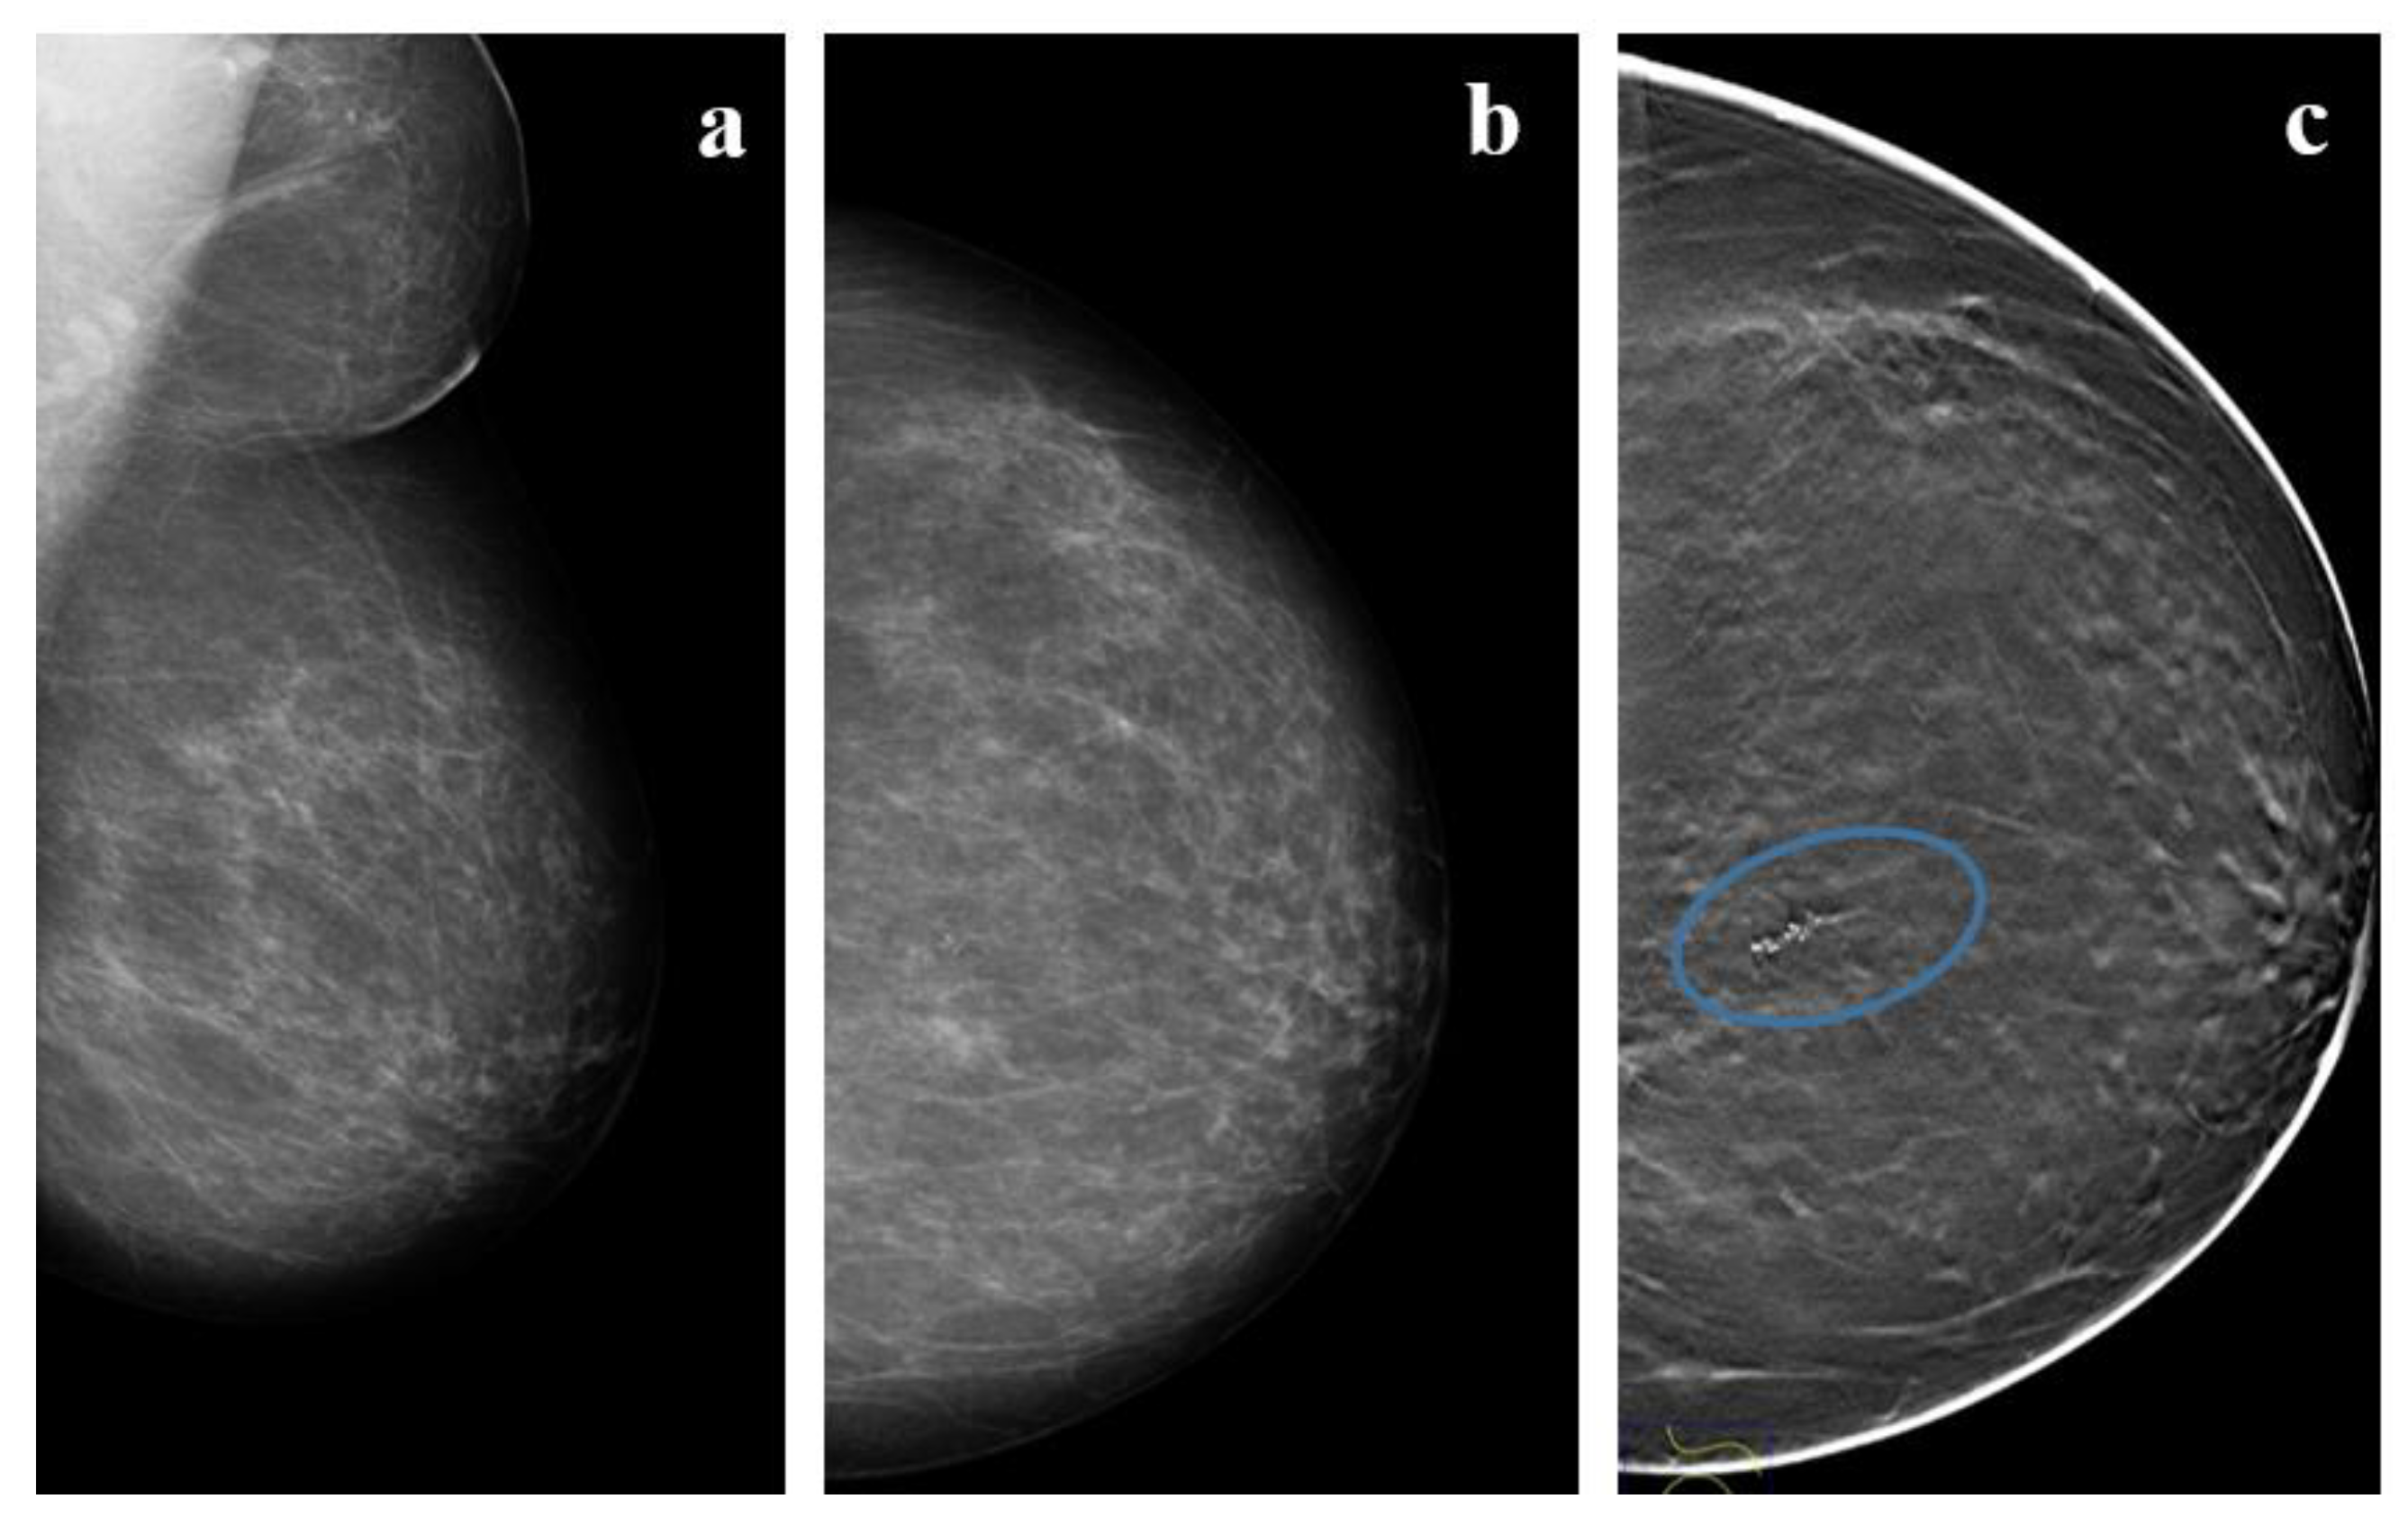

Figure 2. A 57 year-old woman with high-grade DCIS. (a,b) Mammograms and (c) Tomosyinthesis imaging of the left, almost entirely fatty, breast shows a cluster of fine-linear branching calcifications (circle) in the upper inner quadrant (UIQ) classified using breast imaging-reporting and data system (BI-RADS) as Category IVc.

Although the type of microcalcifications is unrelated to the histological subtype (solid, papillary, cribriform), there is a relatively good correlation with tumor grade: multiple clusters of fine granular calcifications are usually associated with low-grade lesions (LG-DCIS) (Figure 1), while linear, often branching, or coarse granular microcalcifications are commonly found in high-grade lesions (HG-DCIS) (Figure 2 and Figure 3). Mammographic distribution of microcalcifications is commonly used as a guide to assess DCIS size or the dimension of the involved area. As the distribution of microcalcifications may be heterogeneous, including missing areas, it should be borne in mind that the real extension of DCIS lesions could be underestimated by mammography [10]. Tomosynthesis, a new three-dimensional (3D) mammographic imaging technique, is emerging as a new screening tool for improved breast cancer detection, mostly in invasive cancer (Figure 1 and Figure 3). A recent population-based study found that 1 out of 16 cases of DCIS was detected only by tomosynthesis, compared with 28 out of 74 invasive breast cancers.